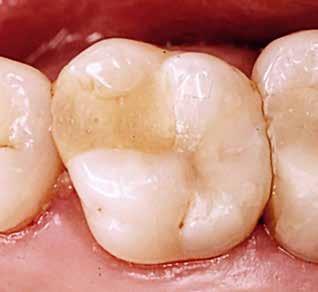

Fig. 1. To røntgenoptagelser,

der viser progression af carieslæsion -54 med 3½ år imellem (A og B), hvor der ses øget penetration af den translucente zone i dentin. Under ekskavering ses kavitet i emaljen samt frakturlinje (C og D, pil sort) svarende til emaljelæsionens ældste og dybeste område (E, sort pil). (©Lars Bjørndal 2023).

A C D E B 469 2024 128 6

Fig. 1. Two radiographs demonstrating an active carious lesion -54 with the two exposures (A and B) being taken with a 3½ year interval. Increased penetration of the translucent zone into the dentine is observed. During excavation, a cavity within the enamel appears, as well as a fracture line (C and D, black arrow) corresponding to the oldest and deepest area of the enamel lesion (E, black arrow). ©Lars Bjørndal 2023.

D E

filmen, og deres produktion af organiske syrer fører til demineralisering af de hårde tandvæv (emalje, dentin og cement). I begyndelsen vil demineraliseringen ikke føre til en egentlig kavitetsdannelse på tandoverfladen til trods for, at der både er mineraltab i emalje og dentin, men den gradvise demineralisering over tid vil ubehandlet kunne svække emaljelæsionens centrale dele. De mastikatoriske kræfter vil føre til dannelse af mikrokaviteter efterfulgt af egentlige kliniske kaviteter (Fig. 1). På sigt fører dette til, at den demineraliserede emaljelæsion bryder sammen og eksponerer den underliggende demineraliserede dentin. På dette tidspunkt siges læsionen at være kaviteret eller klinisk dentin-eksponeret. Hvorvidt en carieslæsion progredierer eller ej, beskrives konceptuelt med begrebet “cariesaktivitet” eller “læsionsaktivitet”. Begrebet dækker både over, hvorvidt der ses akkumulering af biofilm på overfladen af carieslæsionen, samt hvorvidt man klinisk kan se tegn på aktiv produktion af syre i den akkumulerede biofilm. Cariesaktivitet kan tillige bekræftes radiologisk (Fig. 1A og B). En aktiv carieslæsion er kort sagt dækket af en cariogen biofilm og vil derfor progrediere med øget penetrationsdybde af læsionen til følge, hvorimod en inaktiv carieslæsion ikke på samme måde har en overfladebiofilm og heller ikke vil udvikle sig med særlig stor hastighed (1). Om end inaktive carieslæsioner vil kunne aktiveres på ny, er den nuværende kliniske forståelse, at intervention ikke umiddelbart er nødvendigt eller i det mindste kan begrænses kraftigt i tilfælde af inaktive læsioner. Muligheden for akkumulering af biofilm, selv i en kaviteret carieslæsion, afhænger til en vis grad af, hvorvidt carieslæsionen kan beskrives som værende “lukket” eller “åben” (16). Jo færre tandflader der er involveret i en kaviteret carieslæsion, jo mere “lukket” eller “skålformet” vil læsionens topologi være (Fig. 2A-E), hvilket tillader akkumulering af biofilm i læsionsmiljøet. En carieslæsion med et lukket læsionsmiljø vil derfor som oftest være en aktiv læsion, hvorimod åbne carieslæsioner ikke vil kunne akkumulere biofilm i samme omfang og derfor vil forventes at have en tilsvarende lavere progressionshastighed til trods for et ellers fremskredent stadie. Aktive dentin-caries-læsioner dækket af biofilm vil klinisk kunne beskrives som værende hvidlige/gullige/lysbrune (Fig. 2H-I), og den carierede dentin vil være blød og ikke mindst fugtig eller våd. I modsætning hertil fremstår inaktive læsioner mørkfarvede, læderagtige og uden nævneværdig akkumulation af biofilm (Fig. 2I). Desuden udviser inaktive carieslæsioner ikke samme grad af fugtighed (22). Progression og spredning af en aktiv carieslæsion vil ikke blot føre til øget penetrationsdybde, men også lede til underminering af emaljen. Dette kan ses som retrograd demineralisering (Fig. 2H). I takt med at carieslæsionen gradvist underminerer emaljen, vil emaljen på et tidspunkt være så u-understøttet, at den almindelige tyggefunktion vil føre til, at emaljen knækker af. Et resultat af dette er, at carieslæsionen bliver mere “åben”. I den nu relativt mere åbne carieslæsion vil akkumulering af biofilm ikke kunne finde sted i samme omfang som før (Fig. 2I), og carieslæsionens progressionshastighed eller aktivitet vil mindskes eller stoppe fuldstændigt (16,23). Dette dynamiske skift imellem aktivitet og inaktivitet kan ses ved både dybe og mindre dybe carieslæsioner og danner fra et klinisk perspektiv